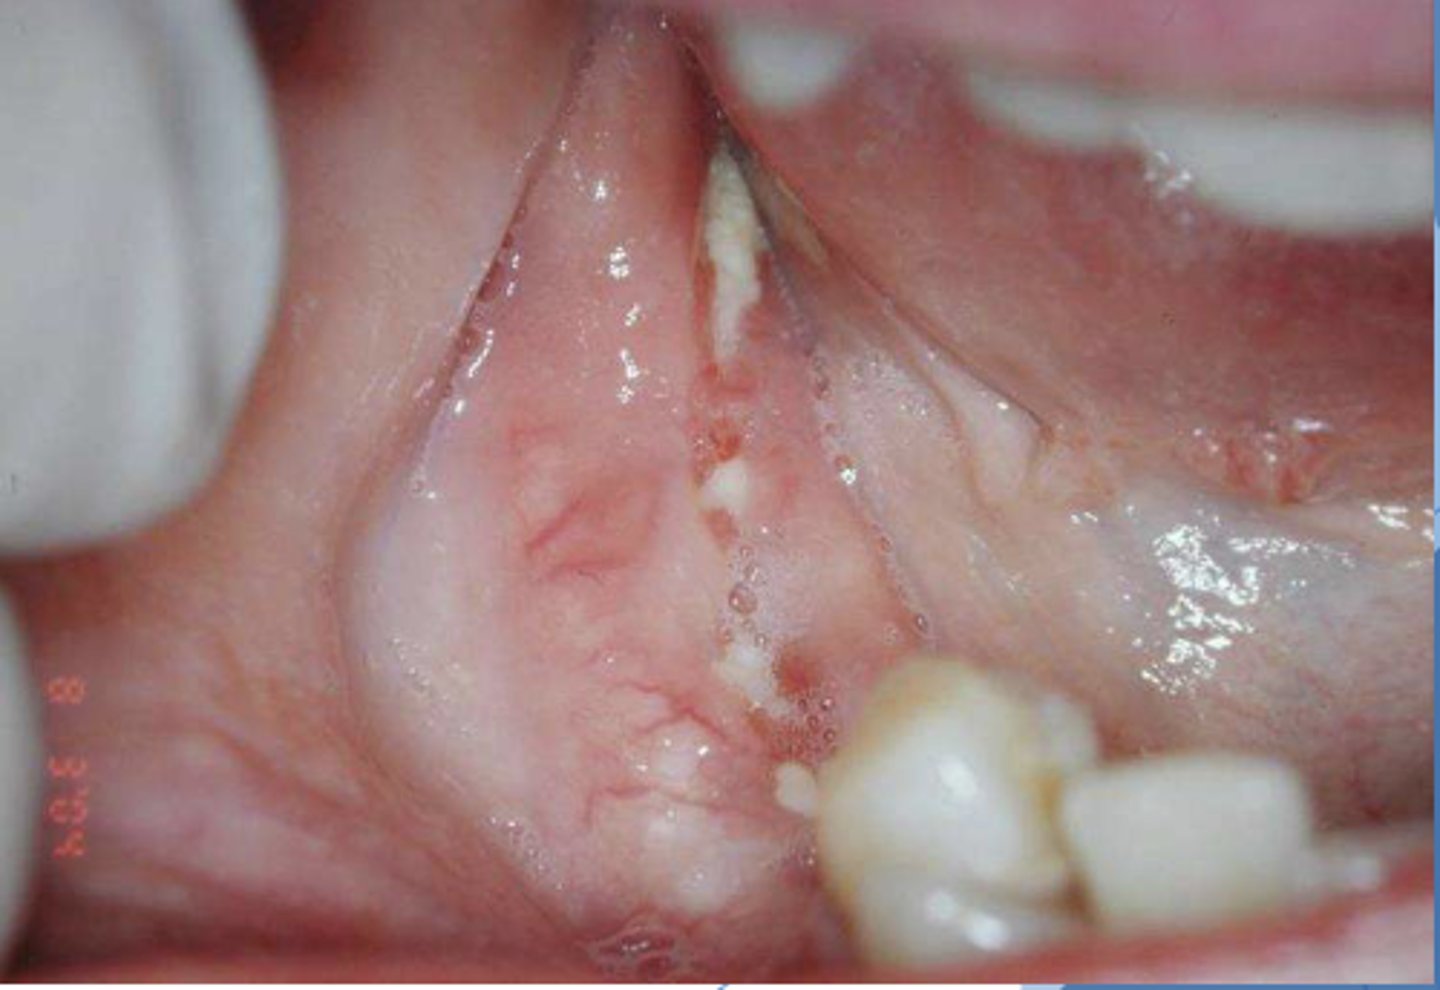

What do you suspect? Patient suspected biting their tongue repeatedly over the past month

traumatic ulcerative granuloma

Patient reported that they accidentally burned their tongue on a cigarette and have since been repeatedly accidentally biting on the lesion. What do you suspect?

Patient reportedly bites their tongue in the same spot a few times per week. What do you suspect?

traumatice ulcerative granuloma

Patient reported biting their tongue for the 5th time this week. What do you suspect?

Patient reported that they accidentally burned their tongue a few weeks ago and the sore gets irritated every time they chew. What do you suspect?